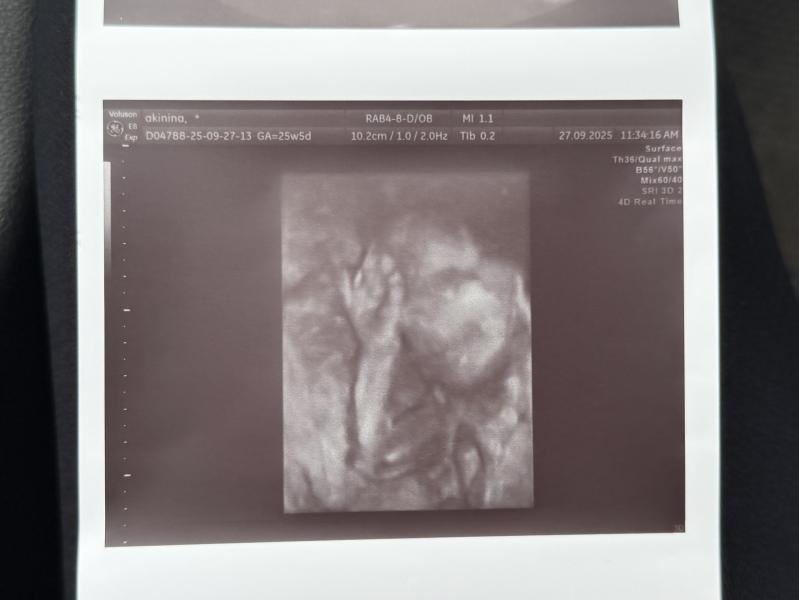

Девочки, сходила на узи, мои боли это слава богу не что-то страшное, просто так вот тянется мой животик)) пошла к очень хорошему специалисту, не ожидая, что там будет 3Д узи))) умиления просто моего не было придела😭😭😍😍😍🥰 хоть и мало что видно отчетливо, но там такая сладкая булочка!!! Жду теперь 28-29 неделек, чтобы сделать красивые фоточки для доченьки))

На фото вот улыбаемся и машем)))